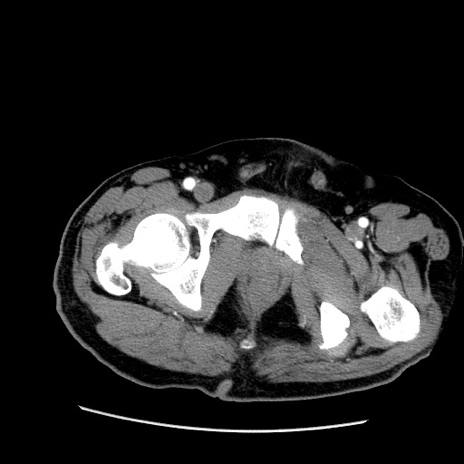

症例22(横断像)

【症例】50歳代男性

【主訴】腹痛

【現病歴】AVMからの被殻出血のため回復期リハ病棟入院中。 本日午後3時頃急に下腹部痛が出現した。

【既往歴】AVM、被殻出血、虫垂炎、高血圧

【身体所見】意識晴明、左半身不全麻痺、会話の理解は良好、36.5°C、腹部:膨隆、全体に板状硬、下腹部正中に圧痛点あり、反跳痛-、筋性防御不明、右下腹部にope scar

【データ】WBC 9400、CRP 0.06